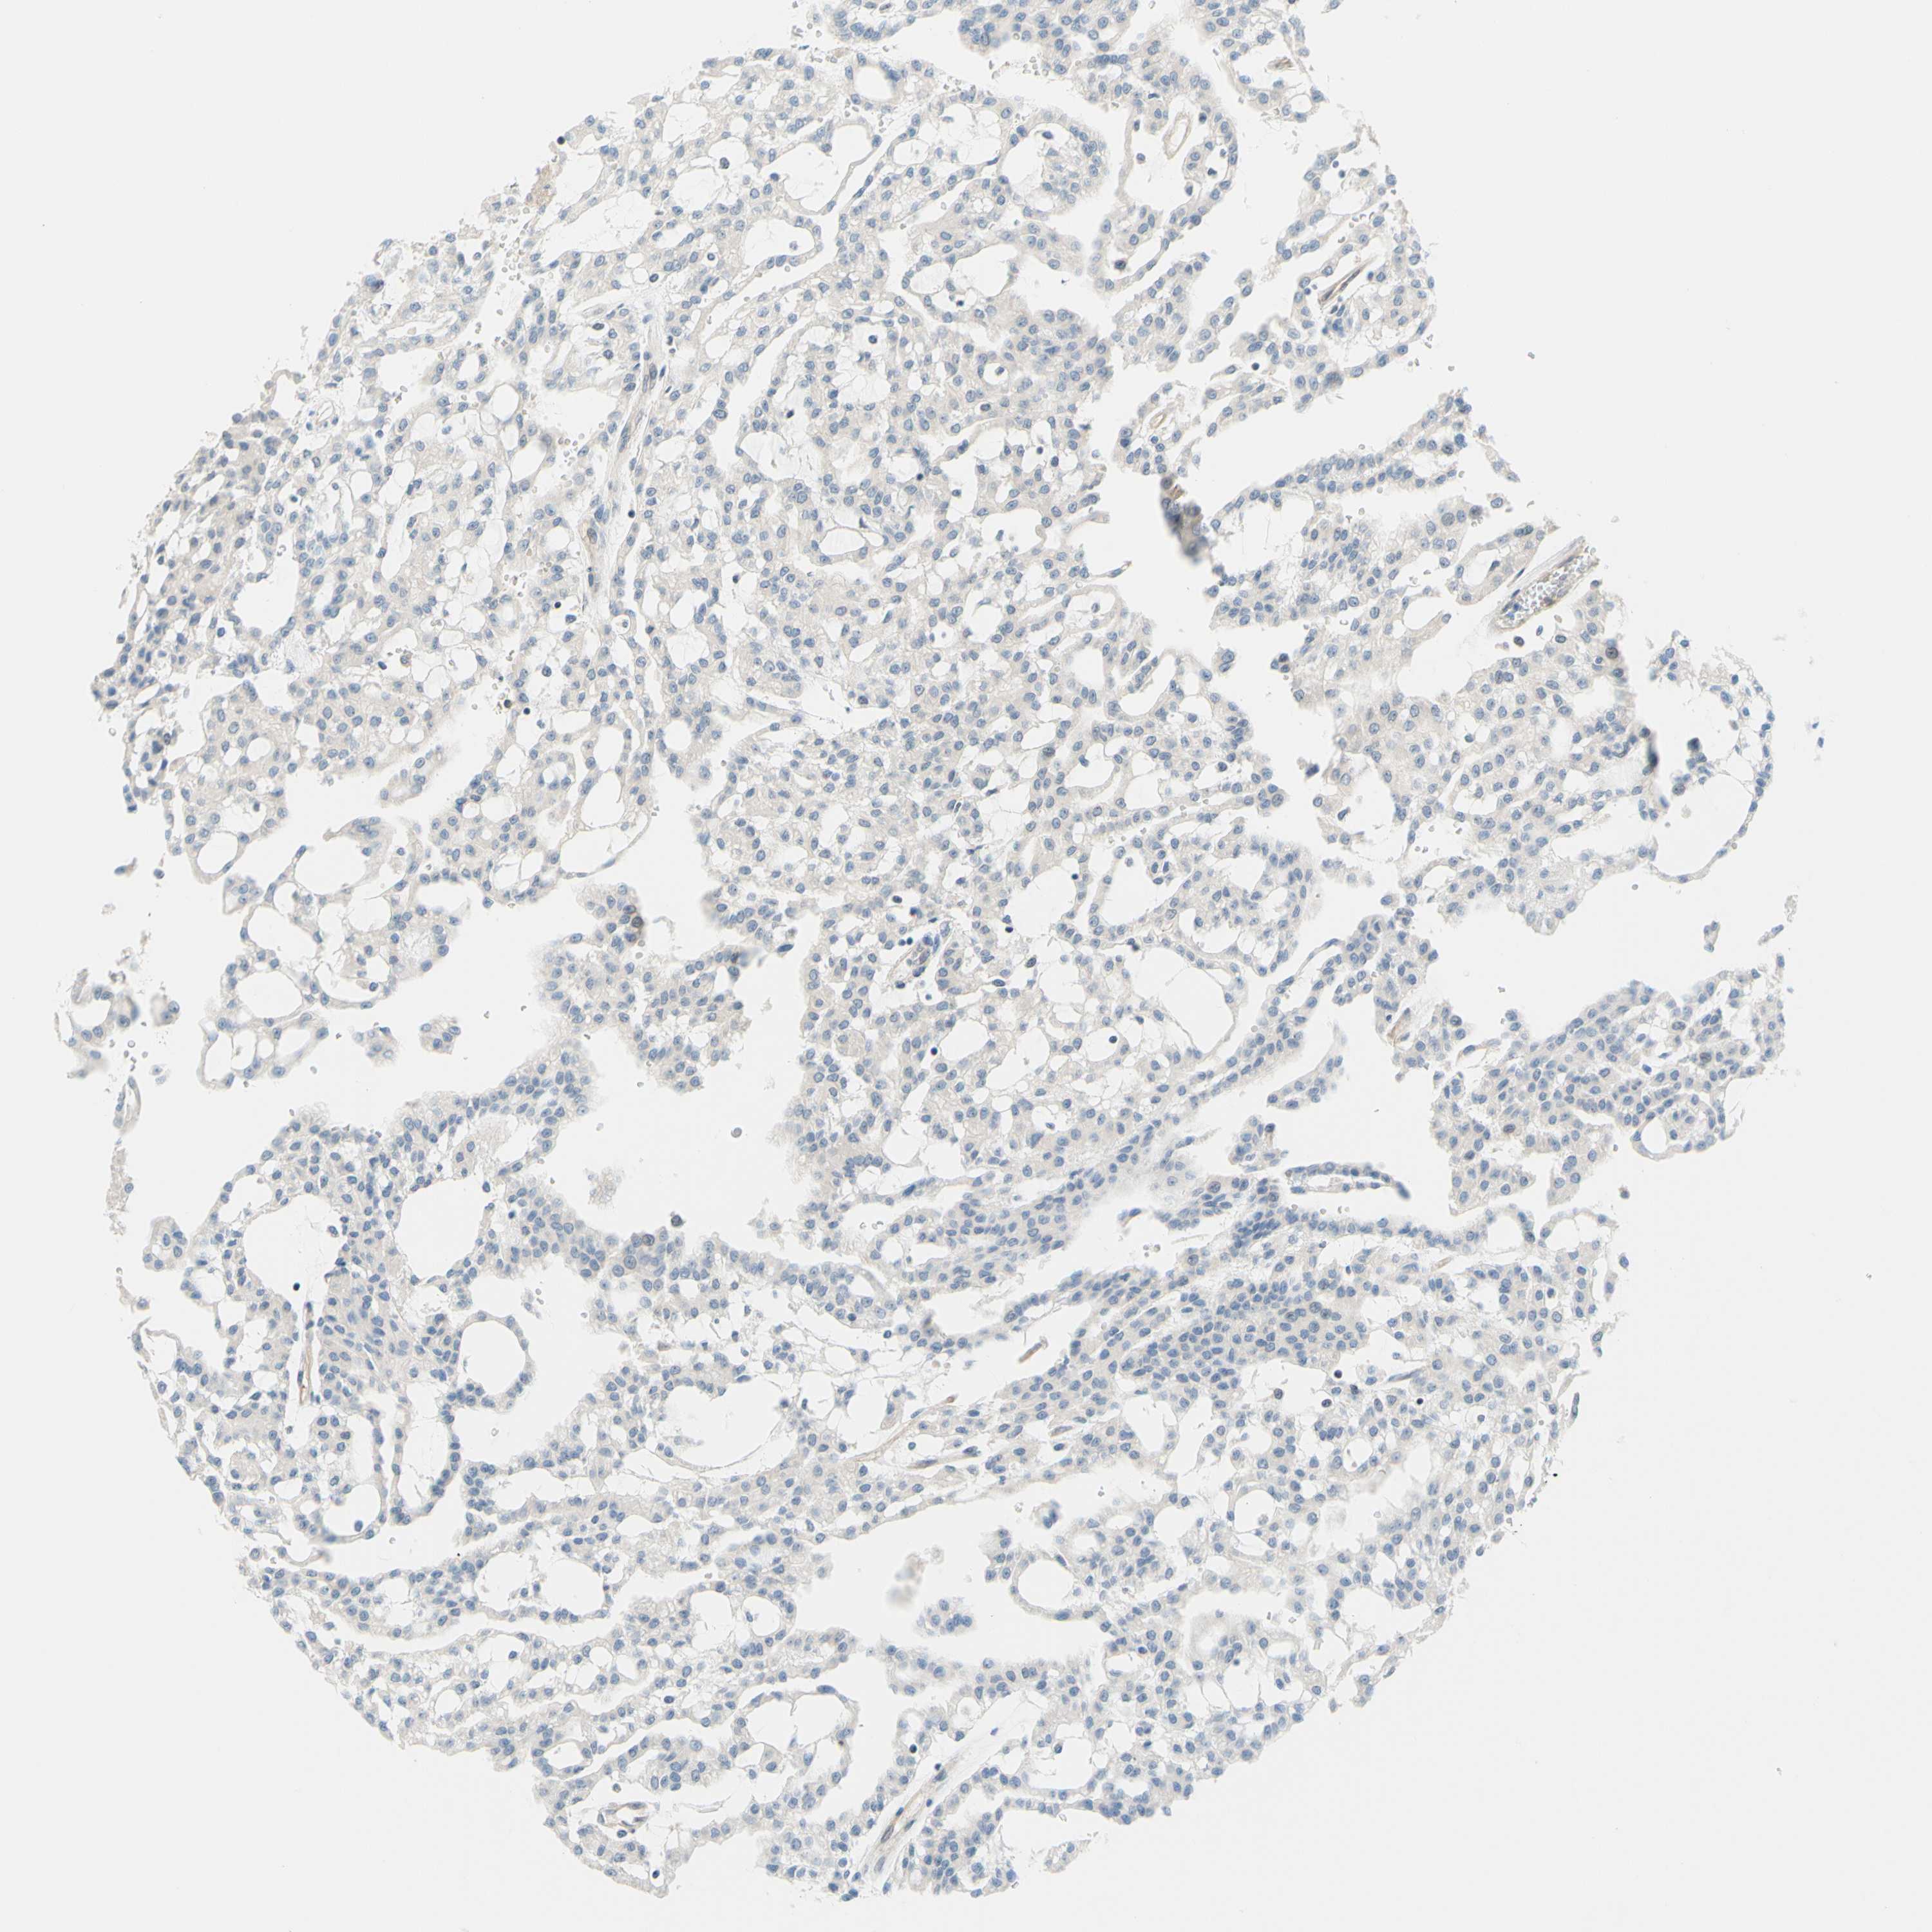

KIDNEY RENAL CLEAR CELL CARCINOMA (VALIDATION) - Interactive survival scatter ploti

The Survival Scatter plot shows the clinical status (i.e. dead or alive) for all individuals in the patient cohort, based on the same data that underlies the corresponding Kaplan-Meier plots. Patients that are alive at last time for follow-up are shown in blue and patients who have died during the study are shown in red.

The x-axis shows the expression levels (FPKM) of the investigated gene in the tumor tissue at the time of diagnosis. The y-axis shows the follow-up time after diagnosis (years). Both axes are complimented with kernel density curves demonstrating the data density over the axes. The top density plot shows the expression levels (FPKM) distribution among dead (red) and alive patients (blue). The right density plot shows the data density of the survived years of dead patients with high and low expression levels respectively, stratified using the cutoff indicated by the vertical dashed line through the Survival Scatter plot. This cutoff is automatically defined based on the FPKM cutoff that minimizes the p-score. The cutoff can be changed by dragging the vertical line or by entering a cutoff value in the square labeled "Current cut-off".

Under the Survival Scatter plot the p-score landscape (black curve; left axis) is shown together with dead median separation (red curve; right axis). Dead median separation is the difference in median mRNA expression between patients who have died with high and low expression, respectively. It is calculated as follows: median FPKM expression of dead patients with high expression - median FPKM expression of dead patients with low expression. This is intended to aid the user in visually exploring custom cutoffs and the associated p-scores and dead median separation.

Individual patient data is displayed and can be filtered by clicking on one or more of the category buttons on the top of the page. Categories describing expression level and patient information include: high, low, alive, dead, female, male and tumor stages. The scale of the x-axis can be toggled between linear and log-scale by clicking on the "x log" button. Mouse-over function shows TCGA ID, patient information and mRNA expression (FPKM) for each patient.

& Survival analysisi

Kaplan-Meier plots summarize results from analysis of correlation between mRNA expression level and patient survival. Patients were divided based on level of expression into one of the two groups "low" (under cut off) or "high" (over cut off). X-axis shows time for survival (years) and y-axis shows the probability of survival, where 1.0 corresponds to 100 percent.

C2CD2L is not prognostic in Kidney Renal Clear Cell Carcinoma (validation)

Best expression cut offi

Based on the FPKM value of each gene, patients were classified into two groups and association between prognosis (survival) and gene expression (FPKM) was examined. The best expression cut-off refers the FPKM value that yields maximal difference with regard to survival between the two groups at the lowest log-rank P-value. Best expression cut-off was selected based on survival analysis .

When clicking on this number, the vertical dashed line indicating cut-off, the interactive survival plot, and the Kaplan-Meier curve will be adjusted to show results based on the best expression cut-off.

: 7.93

Median expressioni

Median expression refers to the median FPKM value calculated based on the gene expression (FPKM) data from all patients in this dataset. When clicking on this number, the vertical dashed line indicating cut-off, the interactive survival plot, and the Kaplan-Meier curve will be adjusted to show results based on the median expression.

: N/A

Median follow up timei

Median follow up time refers to the median time (years) after diagnosis with this type of cancer, based on clinical data from all patients in this dataset.

P scorei

Log-rank P value for Kaplan-Meier plot showing results from analysis of correlation between mRNA expression level and patient survival.

N/A

5-year survival highi

5-year survival for patients with higher expression than the expression cutoff.

For melanoma and glioma, 3-year survival is shown.

5-year survival lowi

5-year survival for patients with lower expression than the expression cutoff.

TCGA RNA samplesi

RNA-seq data is reported as average FPKM (number Fragments Per Kilobase of exon per Million reads), generated by the The Cancer Genome Atlas (TCGA) .

Normal distribution across the dataset is visualized with box plots, shown as median and 25th and 75th percentiles. Points are displayed as outliers if they are above or below 1.5 times the interquartile range. FPKM values of the individual samples are presented next to the box plot.

Average pTPM 7.2

Number of samples 100